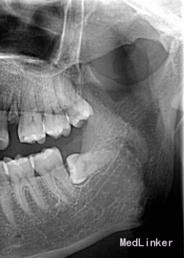

查体 辅查

行曲面断层片